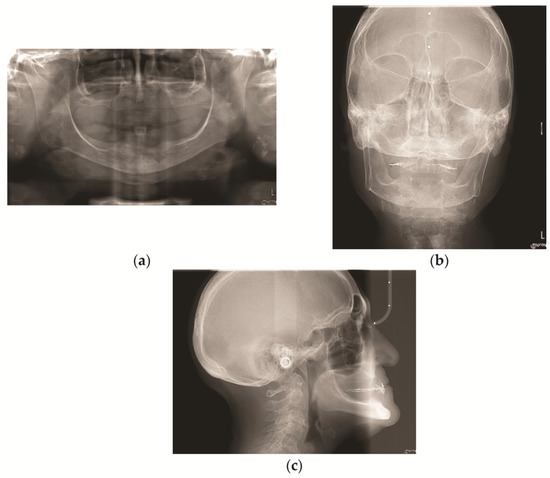

After the anamnestic data collection, a physical examination (intra-oral and extra-oral) was performed and it revealed a generalized muscle and joint pain upon palpation. Keeping the old complete removable prostheses in the oral cavity, occlusal contacts were analyzed, intra- and extra-oral photographs were taken, and routine radiographic examinations were carried out: orthopantomography (OPT) (Figure 2a), antero-posterior teleradiography (AP Ceph) (Figure 2b), and latero-lateral teleradiography (Lat Ceph) (Figure 2c).

Figure 2. Initial radiographic images: (a) initial orthopantomography (OPT); (b) initial antero-posterior teleradiography (AP Ceph); (c) initial latero-lateral teleradiography (Lat Ceph).